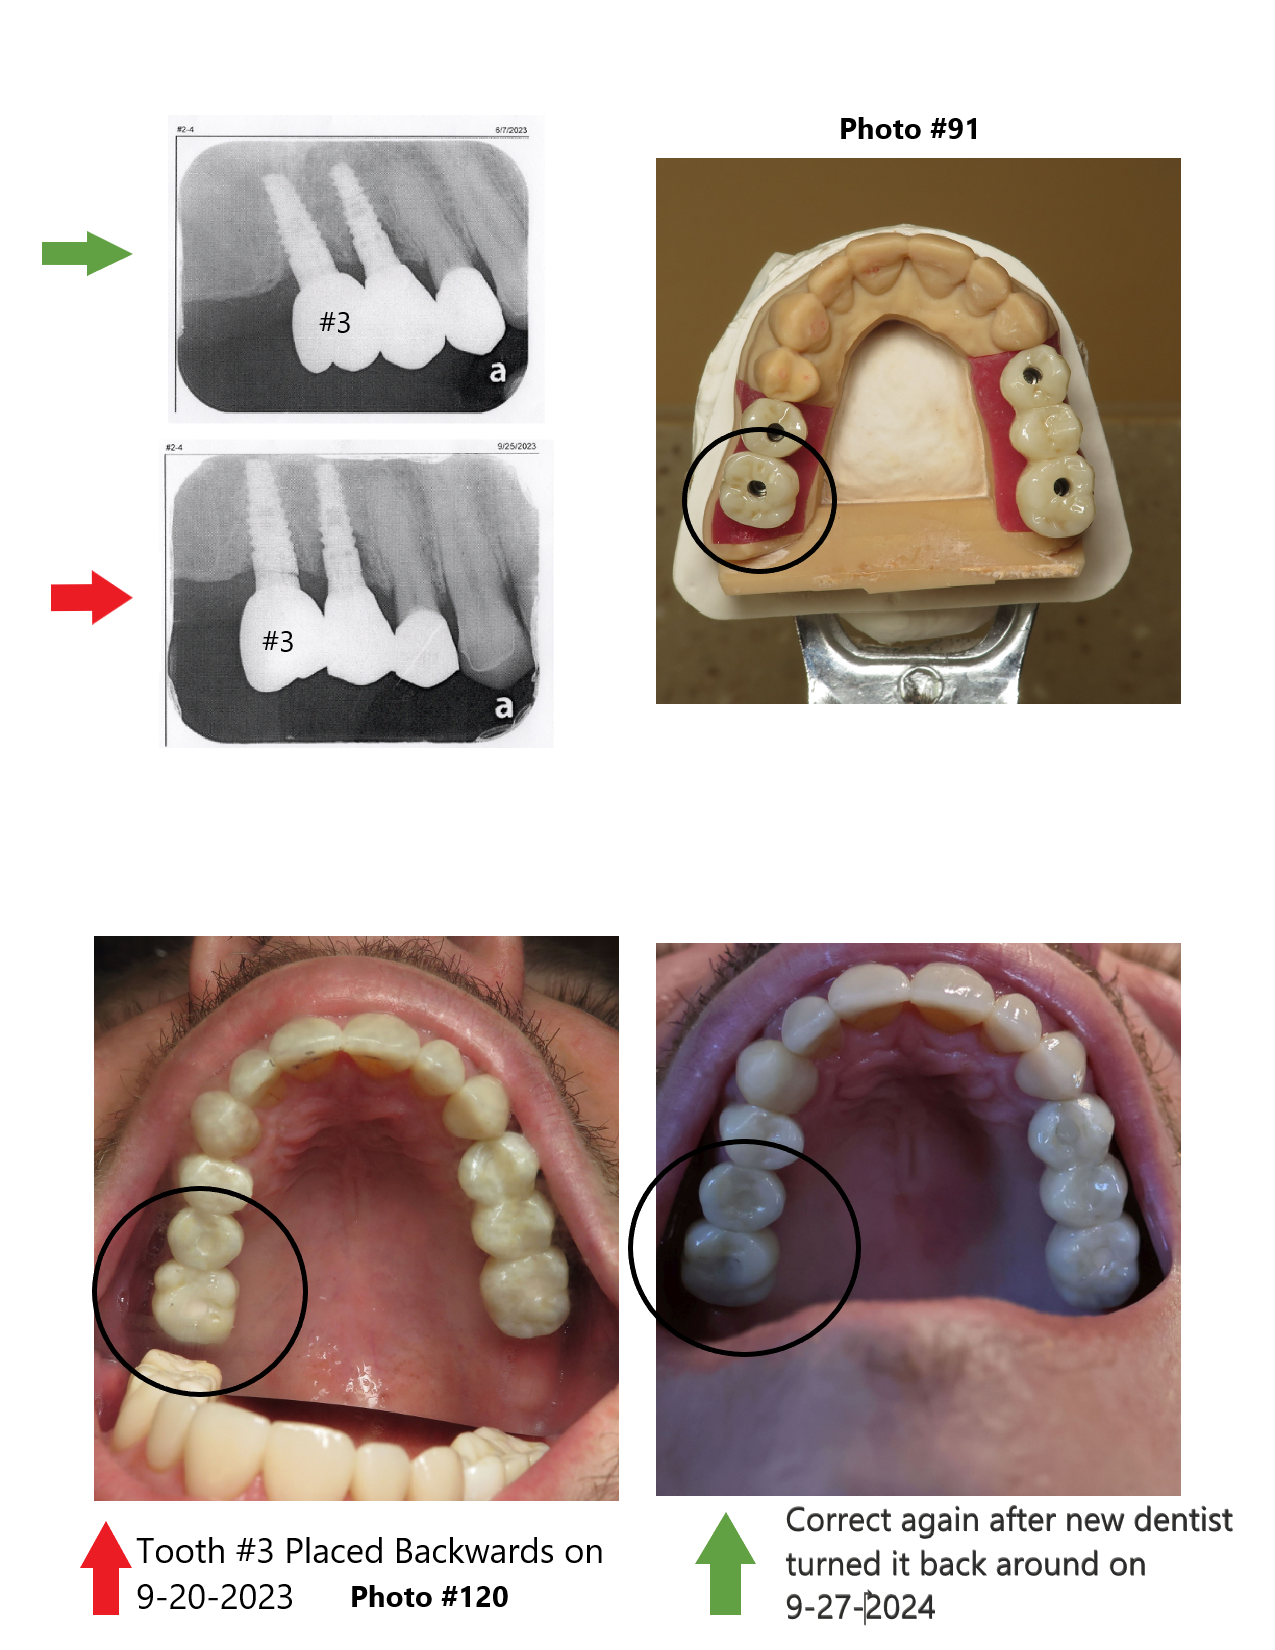

Fraudulent Doctors Doctor doesn't know how to properly do a clinical exam and instead has helped there colleague scam a patient. I am unable to get my teeth fixed because of Dr. Palmer through a biased clinical exam through the Michigan Dental Association with Dr. Palmer where the doctor from Grandville Dental Health Center that did the work was present. Dr. Palmer was bribing me with a check to sign a release form to say the doctor did nothing wrong. Who offers a check to someone before the clinical exam even took place. ...Ā read more